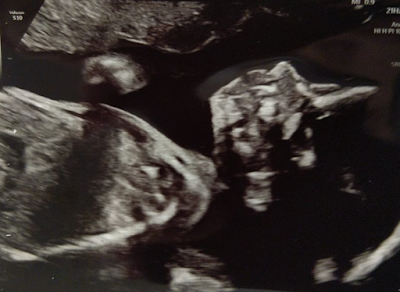

Anomaly Scan at 21 weeks.

We had our scan at 21 weeks and 1 day. Ben laid down and the sonographer first had a look to get a good view of the baby. She spoke to us through the whole scan, what she was looking for and what parts of the baby she was examine in detail. As usual our little rainbow was being shy and difficult. The baby was laying low down with their head tucked against the placenta. Rainbows hands where up against their face and was not moving. The sonographer had to tilt the bed up and give Ben's belly a little shake to encourage our baby to move. Eventually she was able to get a clear view of the babies face, spinal cord and organs. Our rainbow was perfect, was developing very well and their is no signs of any conditions or delay in growth. They were measuring at the right gestational. We got some lovely photos of their foot, hand and face. The sonographier confirm the sex which was what we were previously told at a private scan.

photos of our scan and bump growing.